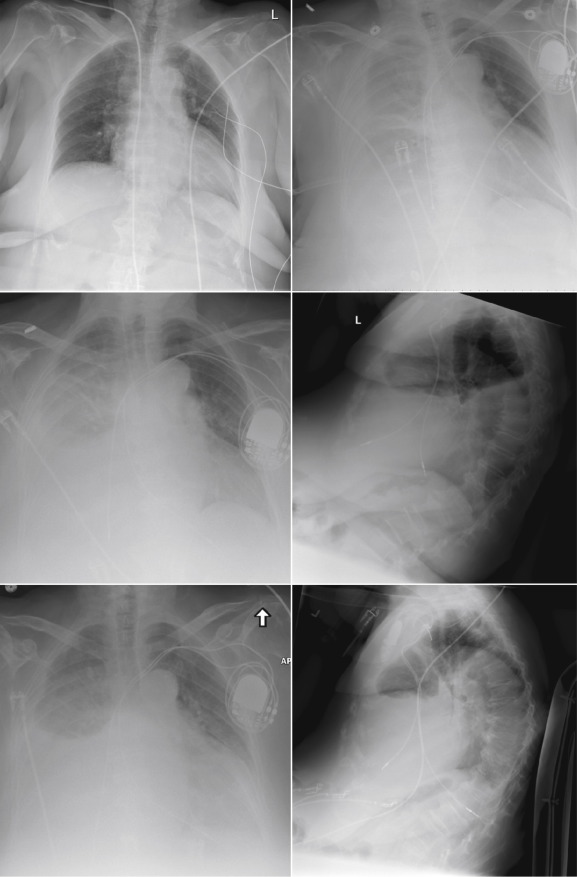

Chest radiography has a standard role in the identification of several potential complications such as pneumothorax, hemothorax, and several forms of malposition after insertion of pacemakers, implantable cardioverter defibrillators (ICDs), and cardiac resynchronization therapy devices.

Pacemaker leads are apparent, and ICDs are more obvious because of their larger coils. Coronary sinus leads for cardiac resynchronization therapy are finer leads.

Endocardial Pacer Leads

The position and integrity of endocardial pacer leads should be verified, especially when pacemaker dysfunction is clinically suspected ( Graphics 23-1 to 23-4 ; Figs. 23-1 to 23-15 ).The most common cause of pacemaker dysfunction that is apparent on the chest radiography is distal lead displacement/misplacement.

With a right atrial lead , the tip should be in the right atrial appendage.

With a right ventricular lead , the tip should lie anteriorly at the apex of the heart.